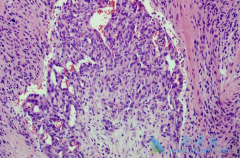

肺癌是目前发病率和病死率最高的恶性肿瘤之一。非小细胞肺癌的靶点检测和靶向治疗是近年来肺癌治疗领域的新突破。但目前的靶向治疗多数集中在非鳞型非小细胞肺癌中,治疗肺鳞癌可选择的靶向药物却较少。本文观察分析了使用 尼妥珠单抗 (泰欣生)治疗肺 ...